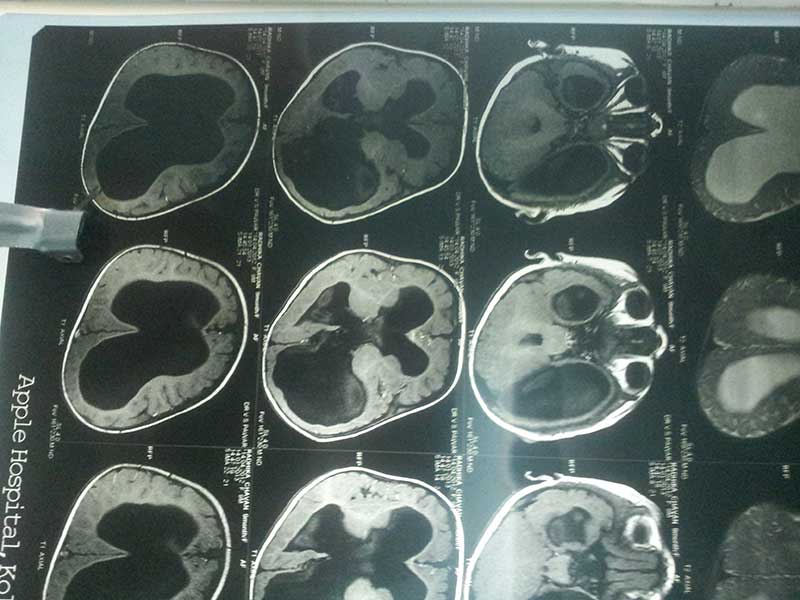

Obstructive Hydrocephalus 2 Pre Op Mri

Hydrocephalus With Cerebellar TB Granuloma

Preop Mri 1